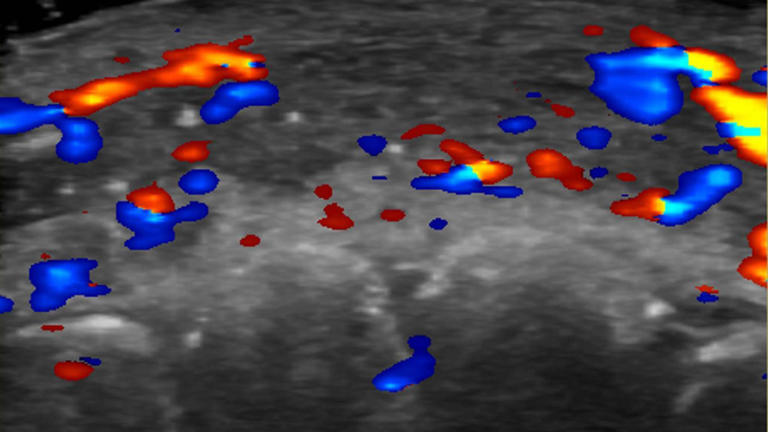

Pesquisadores usaram um ultrassom para estudar 100 casos de preenchimento que deram errado.

Clínicas estão sendo aconselhadas a fazer uma ultrassonografia antes de iniciar o procedimento no rosto, para evitar dandos a artérias próximas.

Em quase metade dos casos avaliados, ultrassonografias mostraram ausência de fluxo sanguíneo em vasos pequenos que conectam artérias superficiais àquelas mais profundas do rosto.

E em um terço dos pacientes, fluxo sanguíneo estava ausente nos principais vasos sanguíneos.

Para evitar complicações, ela aconselha que as clínicas realizem ultrassonografias para planejar onde o produto vai ser injetado.

Se complicações aparecerem, a ultrassonografia pode guiar o tratamento.

"Se os preenchimentos não forem guiados por ultrassonografias, o tratamento é feito apenas com base nos sinais clínicos e o produto é injetado às cegas", afirma Sigrist.

"Mas se nós temos o ultrassom, podemos tratar o local exato onde as obstruções ocorrem."

Assim, em vez de inundar a área com um medicamento chamado hialuronidase para dissolver o preenchimento, os médicos podem realizar injeções guiadas que utilizam menos hialuronidase e proporcionam melhores resultados de tratamento, afirma.